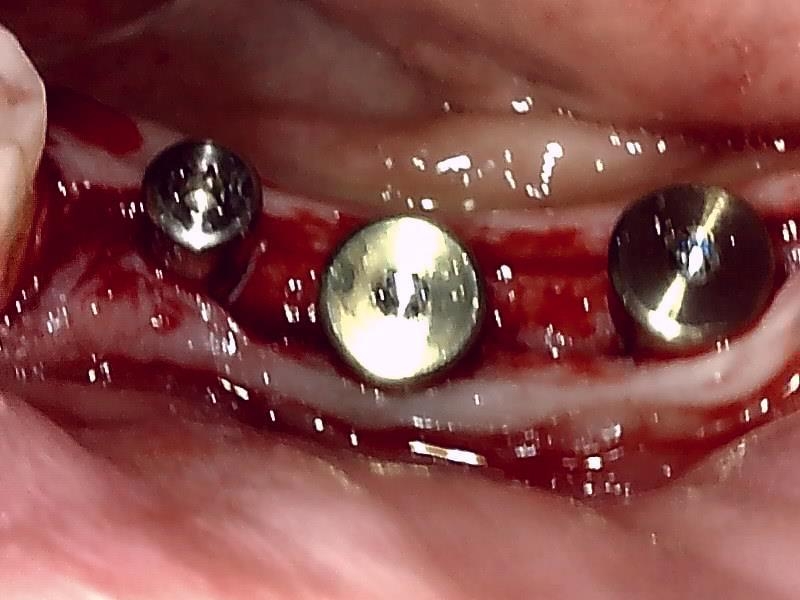

歯肉の整形 (左下)とても綺麗な良い歯肉の状態です。

アバットメント装着 (左下)

(ジルコニアアバットメント)

(ジルコニアアバットメント) (咬合面観)